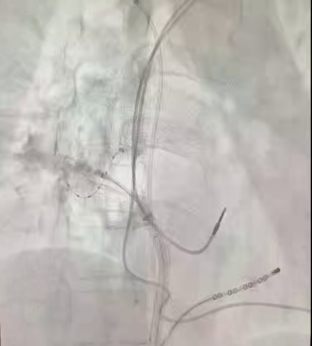

术前将DSA显示系统调整为180°镜像模式。术中,局部麻醉下建立股静脉通路,右侧置入2极和可调弯10极,左侧置入房间隔穿刺系统,通过造影剂确认房间隔穿刺成功,保留导丝置换冷冻球囊系统到左房,依次对左上、左下、右上、右下肺静脉进行冷冻消融,在冷冻至右上肺静脉过程中,转为窦性心律,四根肺静脉房颤相关电位脱落明确,起搏验证确定双侧肺静脉电位隔离,手术顺利完成。

四根肺静脉冷冻消融图